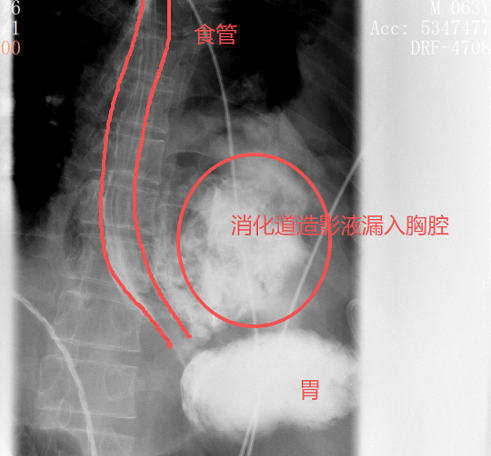

很快,口服钡餐的结果印证了他的判断:钡剂从食道下段的裂口处大量漏出,直接进入了左侧胸腔。

红圈区域是食物残渣、消化液破入食管

手术团队拿着吸引器,一点点清理、冲洗,花了很长时间才将胸腔里的每一点食物残渣都清干净。随后,团队找到了食道下段那道长达10公分的裂口,用可吸收线小心翼翼地完成了分层修补。